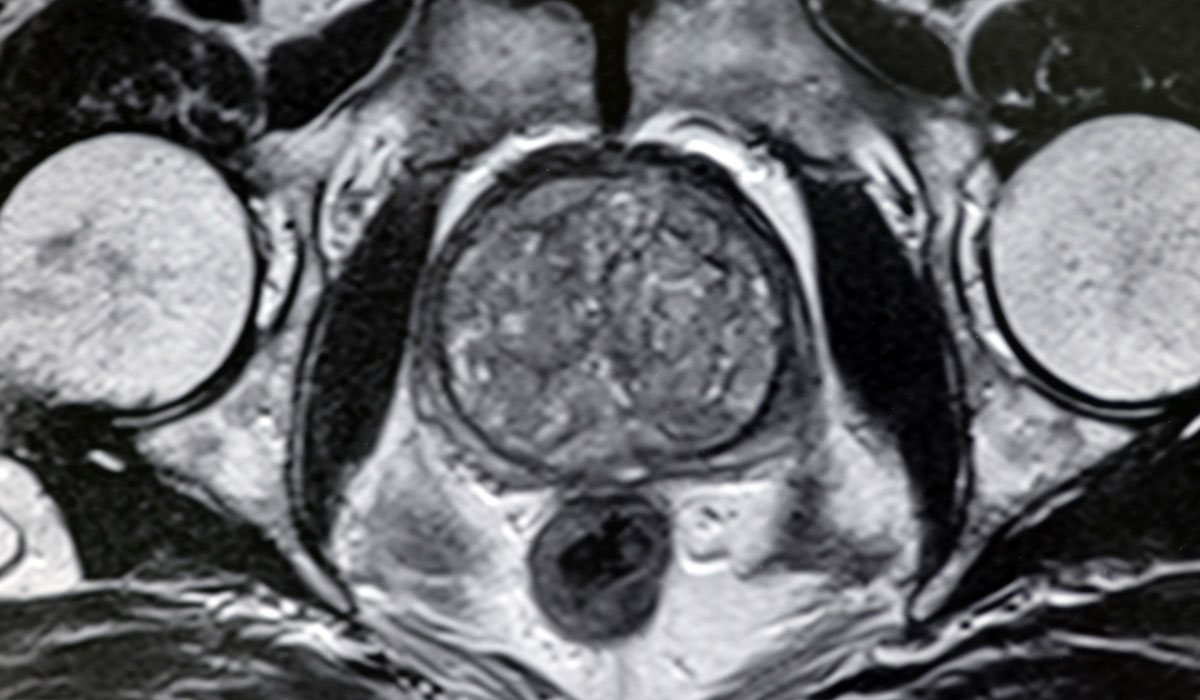

Holmium Laser Enucleation (HoLEP) for BPH

HoLEP surgery. Dr. Miller is one of the top 5 most experienced HoLEP (Holmium laser enucleation of the prostate) surgeons in the world. This laser treats benign enlarged prostate glands to improve urine flow and other urinary tract symptoms. There are only 10 doctors in the U.S. deemed super experts in HoLEP and Dr. Miller is one of them. She attracts patients from across the country.